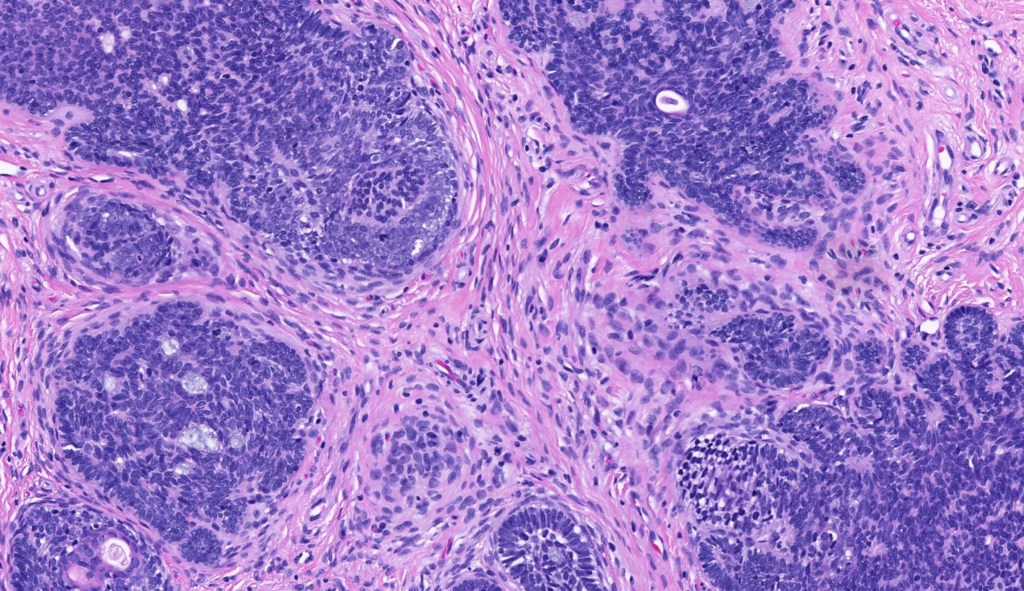

•The classical appearance consists of keratocysts & lobules of basaloid cells

•Basaloid lobules show peripheral palisading

•Mitoses & apoptosis may be present

•Perifollicular mesenchyme is always conspicuous and sometimes densely aggregated are seen indenting the baslaloid lobules (papillary mesenchymal bodies)

•Narrow epithelial strands arising from the basaloid lobules are often present

Trichoepithelioma should be distinguished from trichoblastoma since the latter is very rarely syndromic. Trichoepithelioma is largely a dermal tumor whereas trichoblastoma often extends from the dermis into subcutaneous fat or deeper in very large examples. Papillary mesenchymal bodies are much better formed and generally more obvious in trichoepithelioma. Trichoepithelioma must also be distinguished from basal cell carcinoma. Retraction artifact & stromal mucin are features of basal cell carcinoma and not trichoepithelioma. Papillary mesenchymal bodies are not seen in basal cell carcinoma.